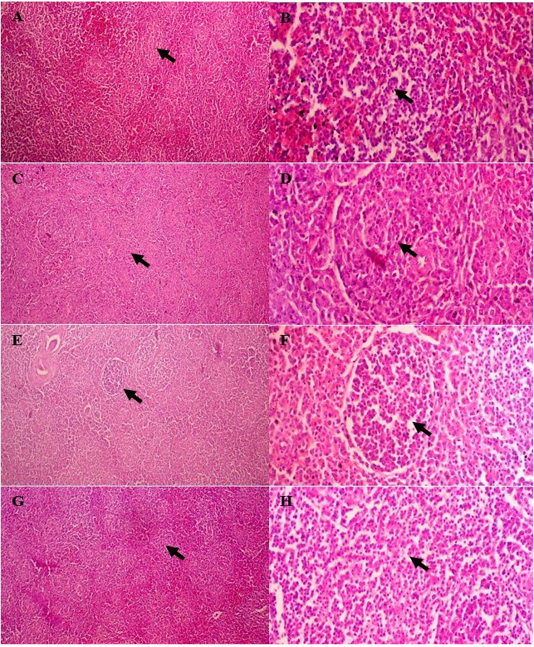

Figure 2

Spleen histopathology of broiler chicken treated with curcumin. White pulp of group I with minimal proliferation of lymphocytes (A and B); mild proliferation of lymphocytes within white pulp of group II (C and D); moderate proliferation in group III (E and F); high proliferation in group IV (G and H). H&E, A, C, E, F (100×); B, D, G, H (400×).